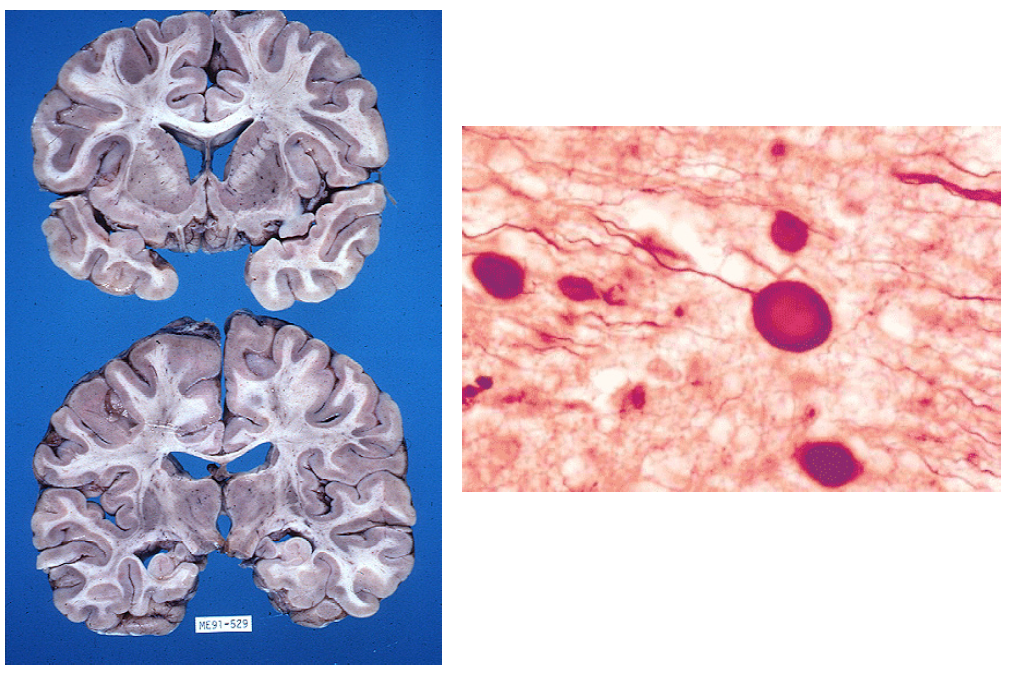

What cell type is circled?

Alive or dead?

When do they appear after ischemia?

Neurons become brightly eosinophilic with loss of the Nisl substance within 6-24 hours of ischemia (“Red neurons”).